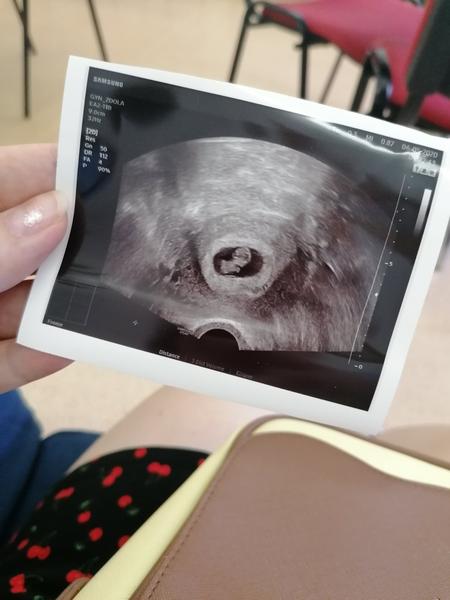

V 8tt miminko nema moc nikde nic. Kolem 11tt uz to byva takovy "gumovy medvidek".

@marta_kovar z této fotky, to nepozná nikdo 😂počkej pár týdnů v 11 tt bude už krásně vidět tělíčko, hlavička i ručičky a nožičky😉